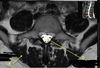

What is letter A?

L4-5 HNP

What is letter B?

S1 VERTEBRAL BODY

What is letter C?

L5 VERTEBRAL BODY

What is letter D?

L2-3 DISK SPACE

ABDOMINAL AORTA

INTERVERTEBRAL DISC

FACET JOINT

SPINOUS PROCESS

What is letter E?

LAMINA

What is letter F?

SUPERIOR ARTICULAR PROCESS

What is letter G?

SPINAL CANAL

What is letter H?

INFERIOR VENA CAVA